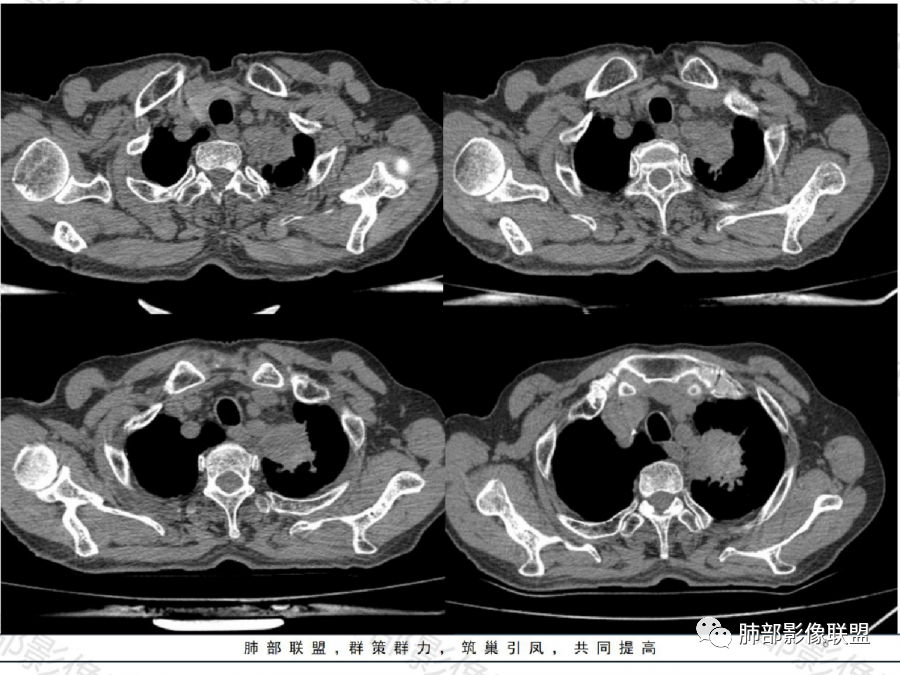

影像表现特点:左肺上叶纵隔旁主动脉弓上方实性肿块影,不规则,膨胀性生长,有棘状突起及收缩,肿块内密度不甚均匀,隐约见小钙化灶。周围具有一定的分叶及长短不一的毛刺征象,外围有小斑片影。矢状位显示支气管截断。增强扫描病灶不均匀强化,内部见小片状的坏死,呈典型的“沼泽样”改变。总体分析恶性征象更多。支持肺癌-鳞癌,支气管截断具有强烈提示意义。